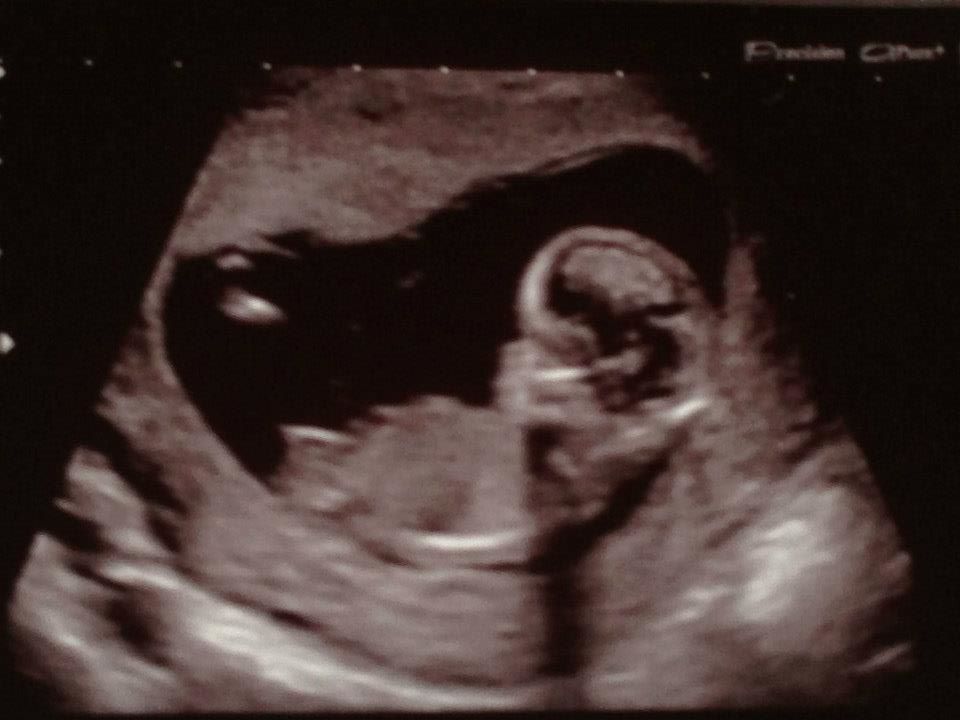

Girl going on head shape and lack of clear nub...

Really i thought that white ish colour thing was a nub ?

I'm no expert but going on the numerous pictures of nubs I've looked at, I'd have to agree with you that that whitish line is the nub, in which case I'm guessing girl :)